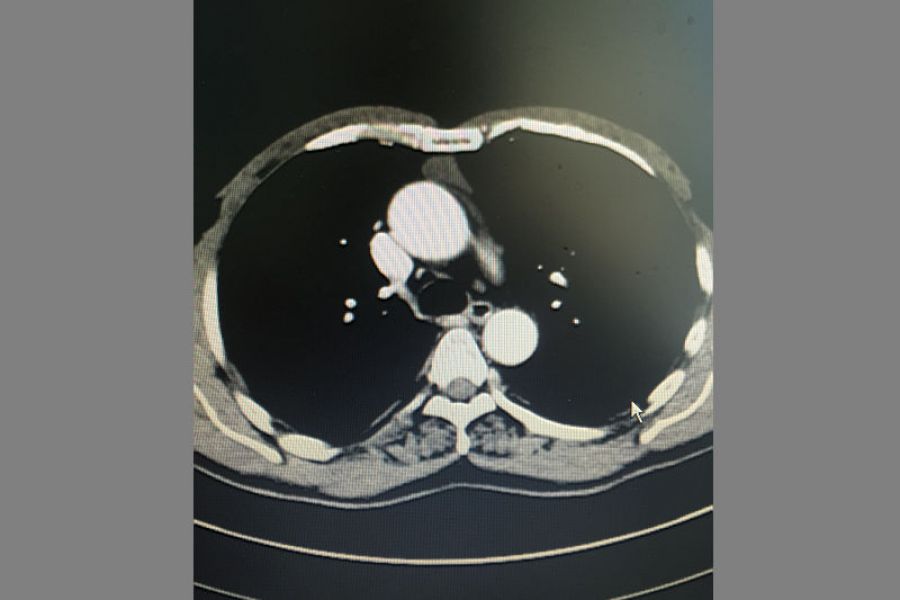

患者王某某40岁,因右胸阵发性疼痛1年入住我院疼痛科,检查发现前上纵膈肿瘤。经心胸外科钟强主治医师会诊后转入心胸外科。转入后予积极完善相关检查,排除相关禁忌症,考虑患者年轻,对创伤小、美观等要求,经研究决定予行胸腔手术。手术入路选择经剑突下切口,黄勇科主任及向加树副主任临场指导,术中杨智杰副主任医师、张建军主治医师及左选健住院医师密切配合,仔细解剖,历经2小时手术完整切除肿瘤。术后患者无明显并发症,主诉疼痛感轻,恢复良好。

纵膈肿瘤影像学表现